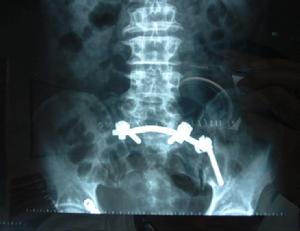

2.手術治療對反覆發作、症狀嚴重者可經後路暴露行骶髂關節融合術。